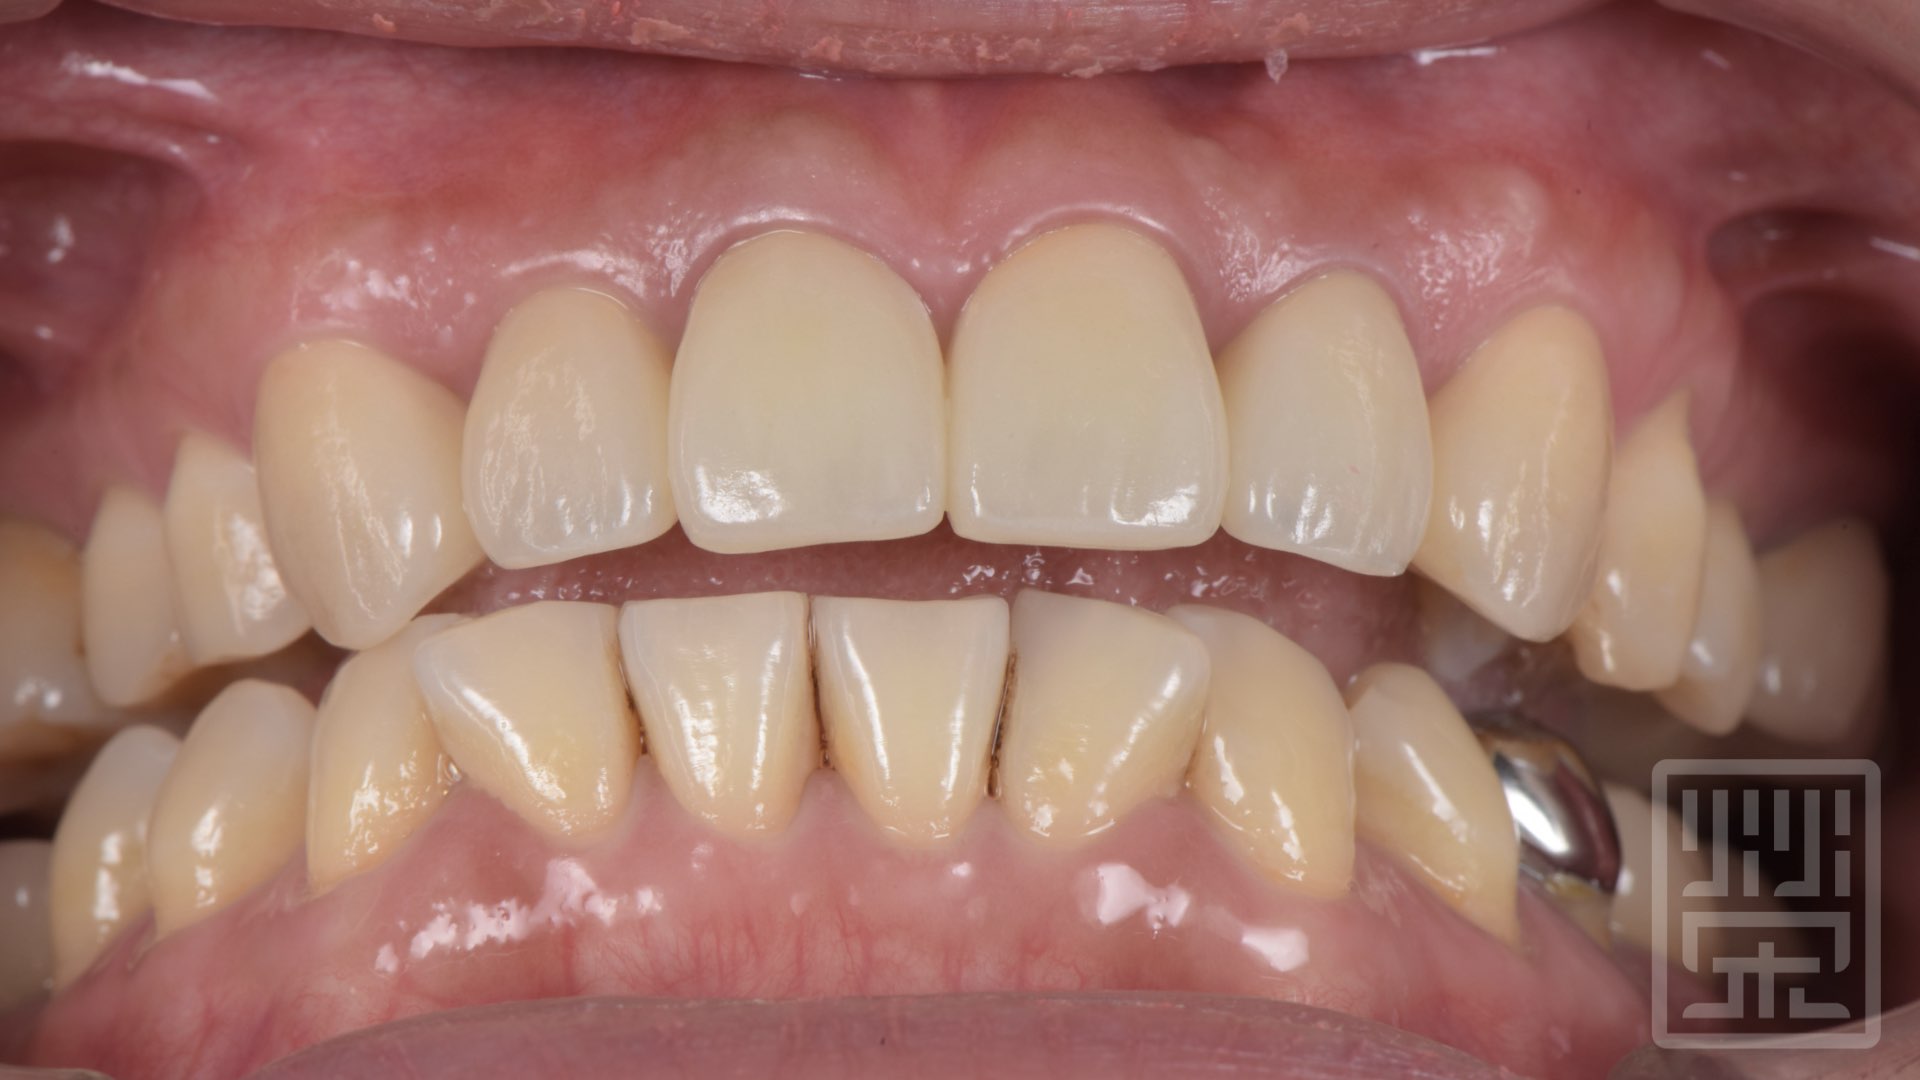

保護性咬合